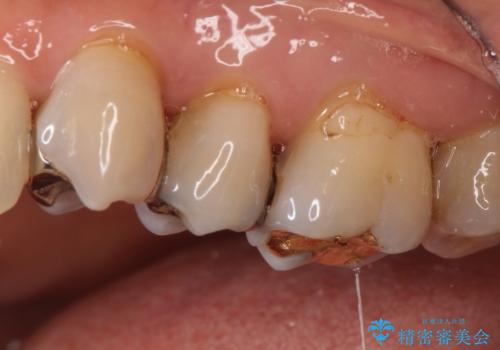

- 363,000円(仮歯11,000円×3本+100,000円×3本)費用は治療当時の料金となります

銀歯を外すとかなり大きな虫歯になっていました。幸いぎりぎりのところで神経まで虫歯は広がっていなかったため、症状が出ない事を確認した後、オールセラミッククラウンで治療しました。虫歯除去後、残っている歯質が少なかったため、破折抵抗を考慮し部分的な被せ物ではなくクラウンを選択しました。

※被せ物では歯と被せ物の適合がとても大切になります。適合が悪い被せもの(歯と被せものの間に隙間がある)を入れるとそこに汚れが溜り虫歯の原因となります。当院では精度が高い被せものを追求するため、サージテル(拡大鏡)や型取りの材料にシリコン材を使用しています。